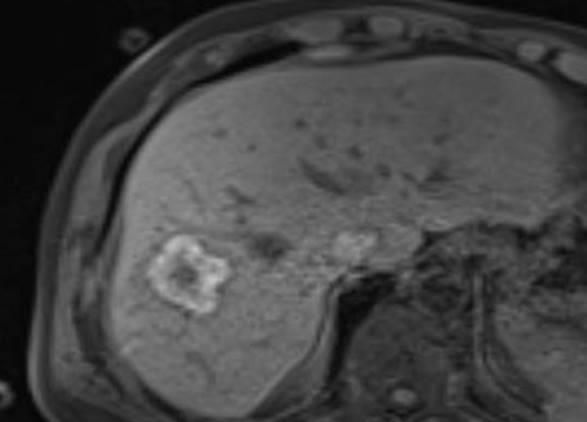

Thermoablation von Lebertumoren

Die minimalinvasive Thermoablation ist eine Therapieoption für Leberkarzinome und Lebermetastasen. Voraussetzung hierfür ist, dass bestimmte Bedingungen wie Tumorgröße, Anzahl und Lage des Zieltumors erfüllt sein. Ob ein Lebertumor mit einem thermoablativen Verfahren (Mikrowellenablation oder Radiofrequenzablation) sicher und effektiv behandelt werden kann, wird vor der Therapie interdisziplinär mit Kollegen aller für diese Fragestellung relevanter Fachrichtungen besprochen.